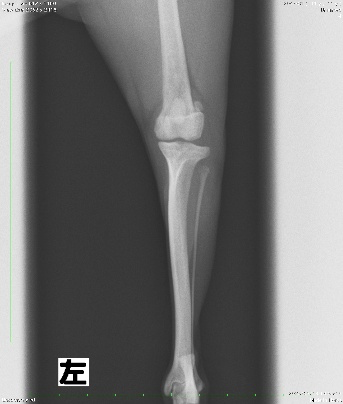

2.X線検査

X線画像を撮影し、脱臼方向の確認や大腿骨と脛骨の骨格変形の有無、変形性膝関節症及び前十字靭帯断裂の併発の有無を確認します。

本症例の術前X線検査所見

本症例は触診と合わせ、膝蓋骨内包脱臼GradeⅡ:症状ありと診断致しました。